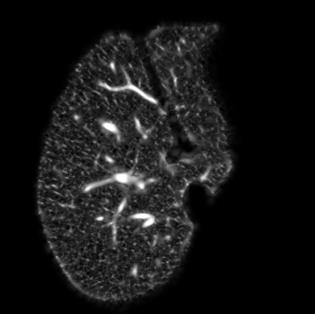

Manually segmenting the hepatic vessels from Computer Tomography (CT) is far more expertise-demanding and laborious than other structures due to the low-contrast and complex morphology of vessels, resulting in the extreme lack of high-quality labeled data. Without sufficient high-quality annotations, the usual data-driven learning-based approaches struggle with deficient training. On the other hand, directly introducing additional data with low-quality annotations may confuse the network, leading to undesirable performance degradation. To address this issue, we propose a novel mean-teacher-assisted confident learning framework to robustly exploit the noisy labeled data for the challenging hepatic vessel segmentation task. Specifically, with the adapted confident learning assisted by a third party, i.e., the weight-averaged teacher model, the noisy labels in the additional low-quality dataset can be transformed from "encumbrance" to "treasure" via progressive pixel-wise soft-correction, thus providing productive guidance. Extensive experiments using two public datasets demonstrate the superiority of the proposed framework as well as the effectiveness of each component.